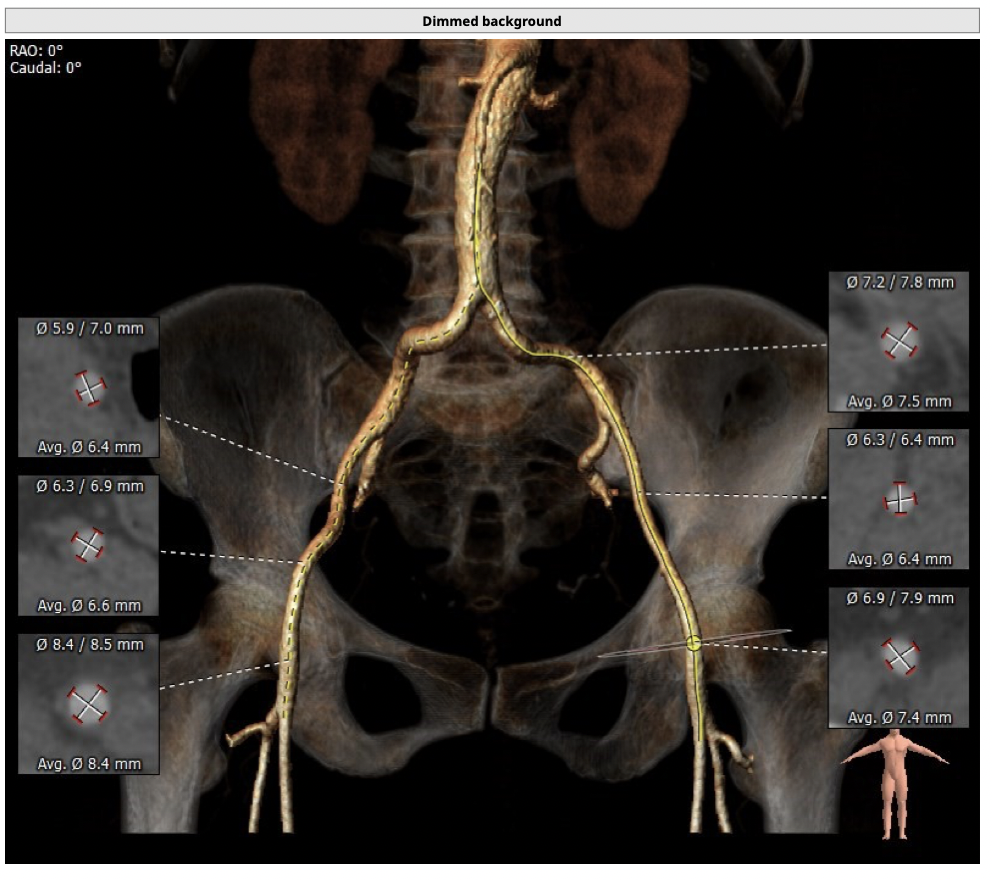

主动脉CT

*髂动脉走形迂曲,升主动脉明显扩张,术中操作需轻柔;